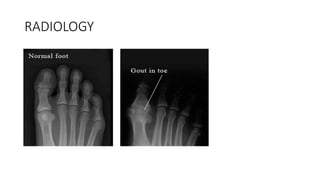

RADIOLOGY